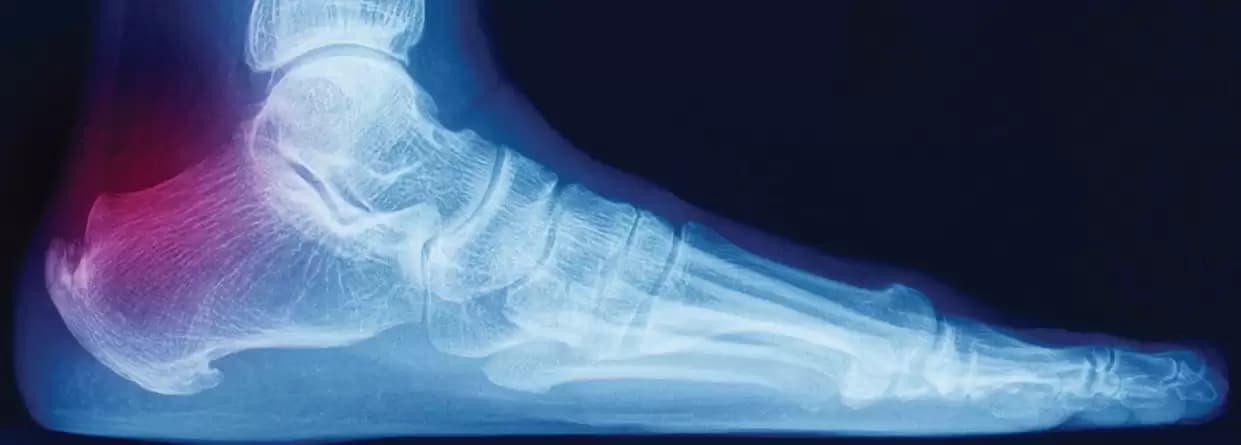

So, they might order an X-ray or MRI test for identifying the heel pain causes such as a bone fracture. However, these tests do not help get a complete look at soft tissues but still are useful to rule out any chances of bone fractures, heel spurs, and other probabilities. With MRI, it becomes easier for the doctor to identify if the plantar fascia has thickened or if there is swelling in the tissues.

Usually, pain in the bottom of the heel is one of the primary signs of plantar fasciitis. There is a probability that your plantar fascia ligament is inflamed and causing you pain. You might find relief with nonsurgical treatment, but that also depends on the cause and the extent of the inflammation. In severe cases, there is a requirement for surgical procedures.

One of the primary plantar fasciitis symptoms is pain at the bottom of your heel or at times at the bottom of the midfoot area. Usually, this condition affects one foot, however, it is not always the case. One can experience the problem in both feet.